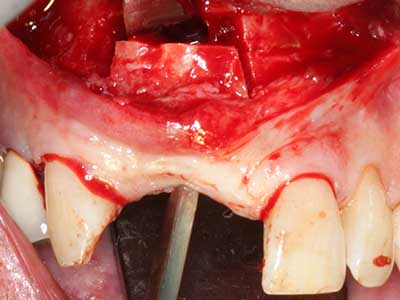

Когато се извършват хирургични процедури върху кост в непосредствена близост до чувствителни структури като кръвоносни съдове или нерви, ротиращите инструменти създават значителен риск за ятрогенно нараняване. Пиезоелектрическите апарати могат да бъдат от помощ при препарация на костно покритие и отстраняване на твърда кост близо до нерви, особено за оголване на нервите след ятрогенно нараняване, както и по време на латерализация на нервите за резекционни и реконструктивни процедури или поставяне на имплант (Фиг. 17-20). Лекият контакт между пиезонакрайника и нерва по принцип не води до нараняване, но ако действате непредпазливо с трионообразни движения или приставки за остатъчен костен субстрат, може да причините временно или перманентно увреждане на нерва. Въпреки това, рискът от увреждане се счита за много по-малък, отколкото при употреба на триони или ротиращи инструменти (Pereira, Gealh et al. 2014).